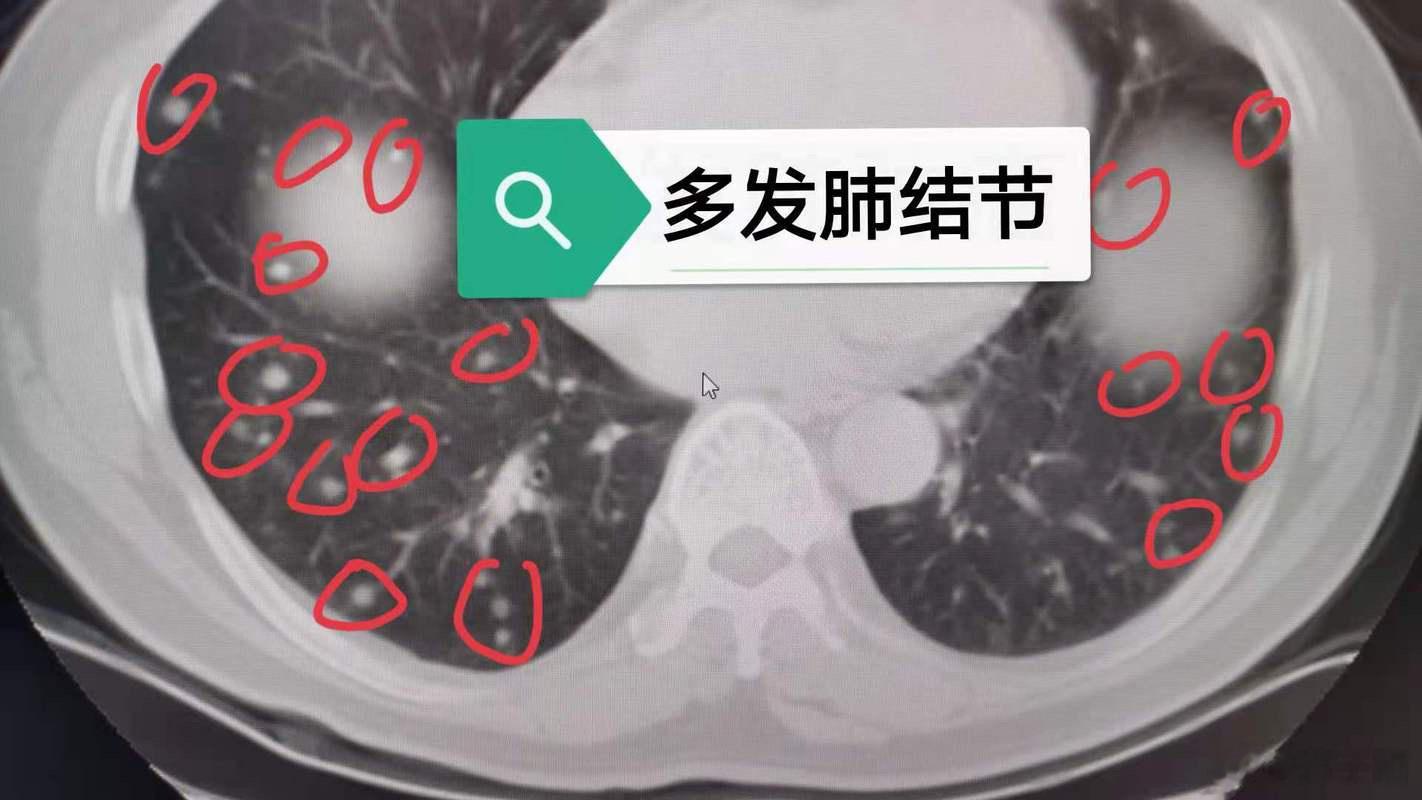

最近很多人拿体检报告来咨询我,肺结节如何调理?

肺结节属于正气不足,痰湿阻塞经络循行、气血不通畅产生结节或淤滞。

中医认为,肺结节的形成多因正气亏虚,痰湿、血瘀积在肺部,气虚、气滞、痰、瘀四者互相影响,导致脏腑功能失调,天长日久积聚而成。中医调理肺结节,一定要因人而异,辨证对待。可以通过使用清肺、润肺、除痰、解郁、软坚、散结的药物、食物,促使肺结节变小,甚至消失。